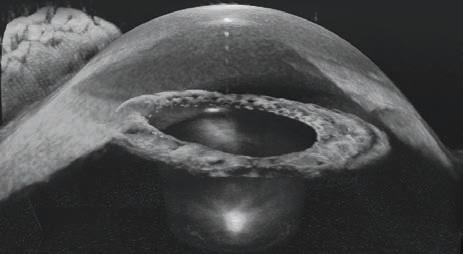

Objective measurements of OSD are obtained through clinical examination and various newer technologies. Factors that should be assessed include eyelid position, tear meniscus, tear film quality, tear quantity (Schirmer’s test), tear film break-up time (TBUT; less than 10 seconds being abnormal), meibomian gland dysfunction and any ocular surface staining with fluorescein.

Clinical examination can be augmented by several new technologies such as tear osmolarity testers and ocular surface analysers which measure lipid layer thickness (LLT), capture blink dynamics, and image meibomian gland structures. These technologies can be helpful in diagnosing OSD and monitoring progression. 8 They can also be used to perform baseline tests before initiating topical glaucoma therapy.